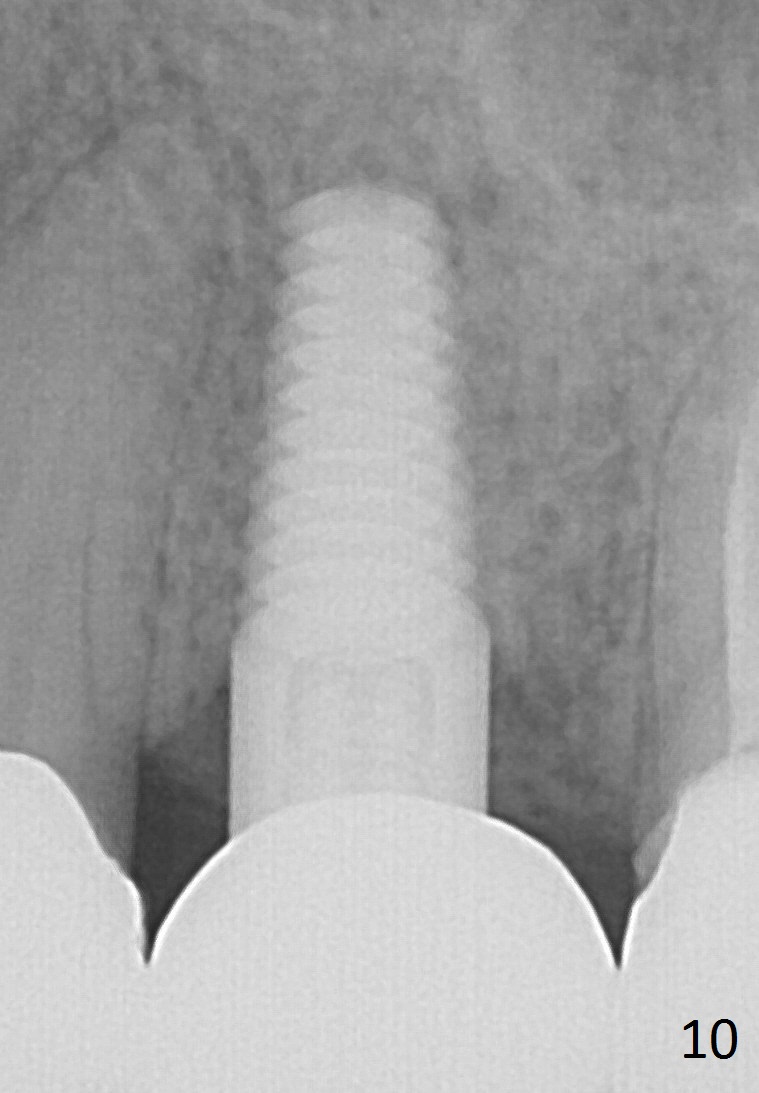

A 45-year-old lady is nervous about dental treatment. The missing tooth #13 was replaced by a 3-unit bridge. The latter is sectioned because the posterior abutment has caries. PA in Fig.1 is taken when root canal therapy and build up are finished. Fig.2 shows the wide edentulous area with a single-unit crown being tried in for #14. Osteotomy is initiated with the crown in place without cementation, since it is easy to determine the mesiodistal position (Fig.3 red lines). Without the crown in place, osteotomy tends to be distal. In this case, the osteotomy is later attempted to be moved distally with Lindamann bur and deepened to 14 mm from the gingival margin (Fig.4). A 2.5 mm reamer is being used at 50 RPM to increase osteotomy with difficulty. Drills have to used at high RPM instead (Fig.5 4x14 mm). A 4.5x14 mm tissue-level implant is placed with insertion torque >60 Ncm (Fig.6 I); a 4x3 mm abutment (A) is placed immediately for an immediate provisional. Fig.7 is taken 7 days postop to show the gingival recipient site formed by the provisional. The patient is so afraid of X-ray that the next one is taken 1.5 years post cementation (Fig.8). It appears that dense bone bundle forms between the crest and the 1st implant thread (adaptation functional change, arrowheads). The bone density continues to increase 2 years 8 months post cementation (Fig.9 *, 10); the bone has grown into the area between the 1st 2 threads (arrow).